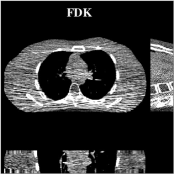

Fig.Β 7 shows the reconstructions (shown for the central axial plane in the 3D volume) for FDK (provided by GE Healthcare), PWLS-EP (corresponds to Fig.Β 8(a)), and PWLS-ULTRA with (corresponds to Fig.Β 9(a)). The PWLS-ULTRA reconstruction has lower artifacts and noise. Moreover, the image features and edges are better reconstructed by PWLS-ULTRA than by PWLS-EP or FDK.

Fig.Β 8 shows the reconstructions (shown for the central axial, sagittal, and coronal planes in the 3D volume) for PWLS-EP with different regularization strengths , denoted as a multiplicative factor of the parameter value in Fig.Β 7. Fig.Β 9 shows the reconstructions for PWLS-ULTRA (with patch-based weights) with different parameter combinations. For the sagittal and coronal planes, we show the central out of axial slices. Larger regularization strengths would achieve more noise reduction but simultaneously lower spatial resolution in PWLS-EP and PWLS-ULTRA, e.g., compare Fig.Β 8 and Figs.Β 9(a) and (d). Larger values of would achieve lower sparsities and more noise reduction but potentially oversmooth the image, e.g., compare Figs.Β 9(c) and (d). Small values of may introduce additional spurious noise in the PWLS-ULTRA reconstruction (compare Figs.Β 9(a) and (b)). Fig.Β 11 shows profiles of chest reconstructions (plotted from the central axial slice) for the PWLS-EP and PWLS-ULTRA methods. The profile locations are shown in green lines in Fig.Β 7. Both PWLS-EP with regularization strength X and PWLS-ULTRA (with patch-based weights) in Fig.Β 9(a) have lower noise than the PWLS-EP with regularization strength X. Though the spatial resolution of PWLS-EP with regularization strength X is close to PWLS-ULTRA in the selected soft-tissue regions, PWLS-ULTRA reconstructs bone and spine areas with higher resolution, and preserves small features better (compare the zoomed-in areas in Fig.Β 8 and Fig.Β 9).